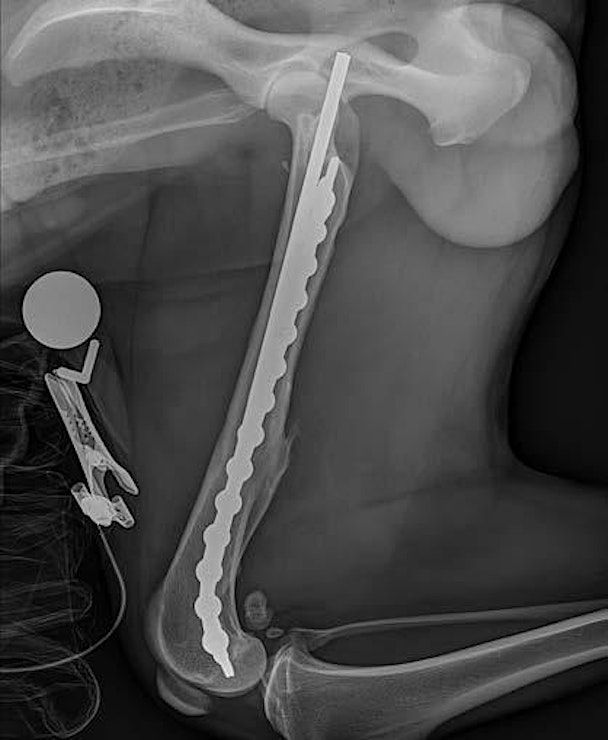

Too often, fractures of the pelvic limb go unoperated. This course gives veterinary practitioners the skills and confidence to conquer seven of the most common orthopedic procedures of the pelvic limb.

Procedures of various degrees of difficulty will be tought:

- Femoral fractures

Femoral fractures